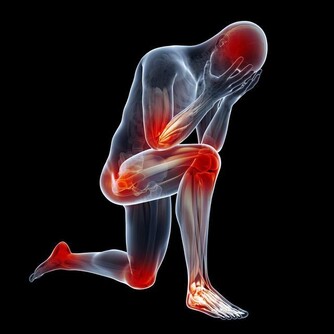

小指短小:提示生育機能弱,腎氣不足,易患頭暈、耳鳴、腰腿酸痛等病。

女性多為子宮小或月經不調;男性多為性功能較弱。

小指蒼白、細小且瘦弱:易患腸道疾病,進而引起吸收不良或排便不暢。

小指過度彎曲:女性卵巢功能差,易患不孕症;男性性功能障礙,易患陽痿早洩等。